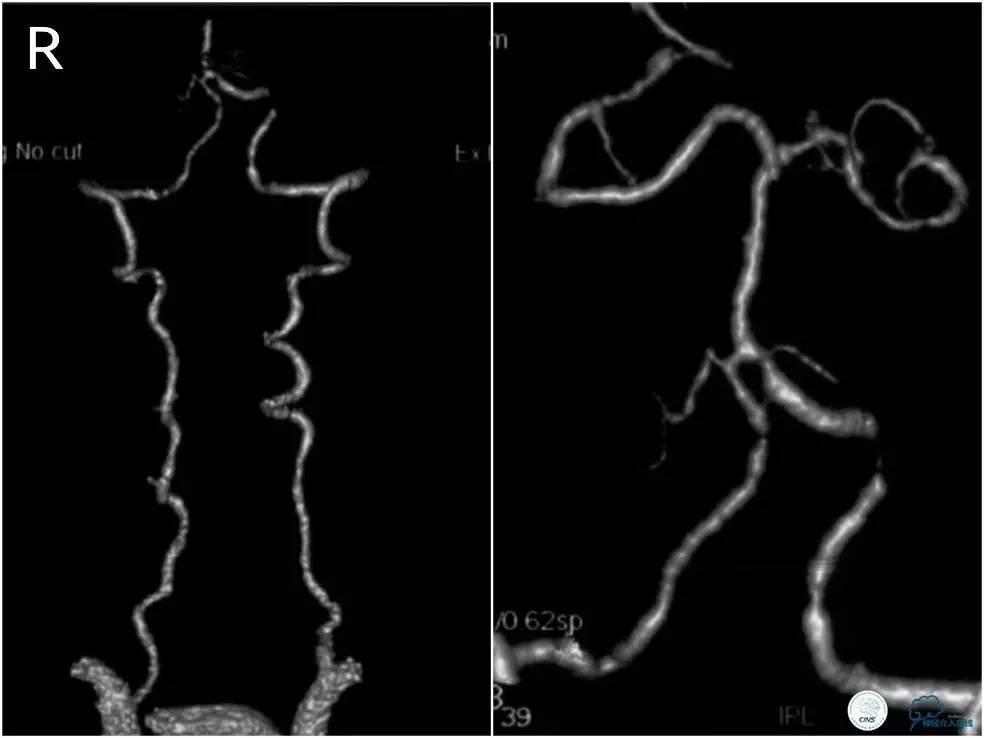

患者,女,61岁。主因“反复头晕伴视物旋转3月”入院。3个月前无明显诱因下出现头晕,伴视物旋转,持续约半分钟后症状缓解。 3天后类似症状反复,持续约1分钟后缓解。就诊当地医院,查头MRI:双基底节区、左额叶缺血灶及软化灶。头颅CTA(图1):颅内多发血管狭窄,左侧椎动脉颅内段重度狭窄。

图1